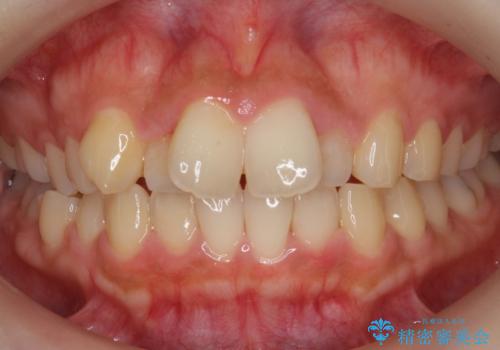

前歯が左右対称じゃない 保険の被せ物をきれいにしたい ホワイトニング併用

- 左上の前歯が小さく左右対称ではないのと、保険の前歯の被せ物のやりかえを希望して来院。

小さい前歯は、反対側と合わせた形にしました。